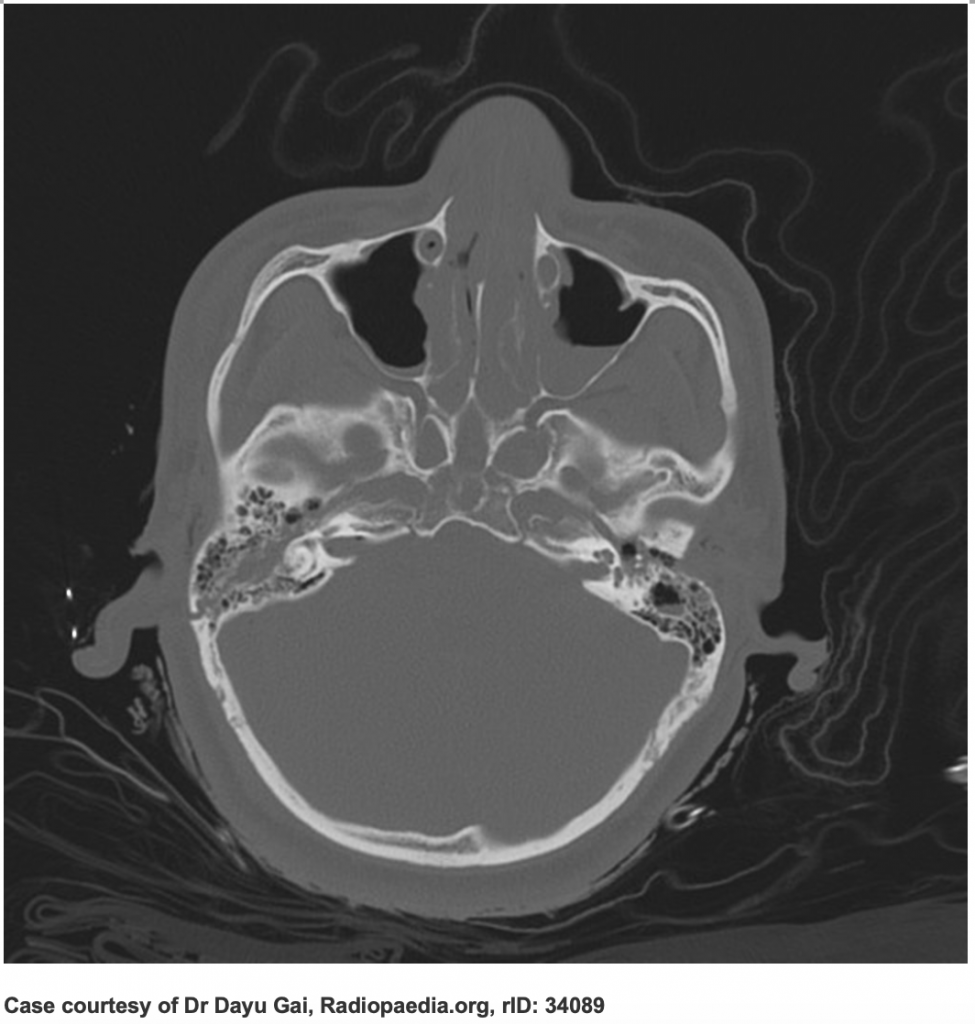

From radiopaedia.org

Image Basilar Skull Fracture Bleeding Ear blood draining from your nose, ear or a wound at the site of an open fracture. open fractures communicate with the skin through a wound, a sinus, the ear, or the oropharynx. basal skull fractures are most frequently diagnosed by clinical findings, making clinical assessment skills critical. Ct may reveal suspicious fluid collections. signs of basal. Basilar Skull Fracture Bleeding Ear.